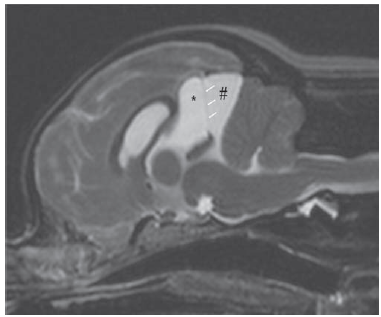

Name the areas marked with an asterisk and hash

• = suprapineal recess

# = quadrigeminal cistern